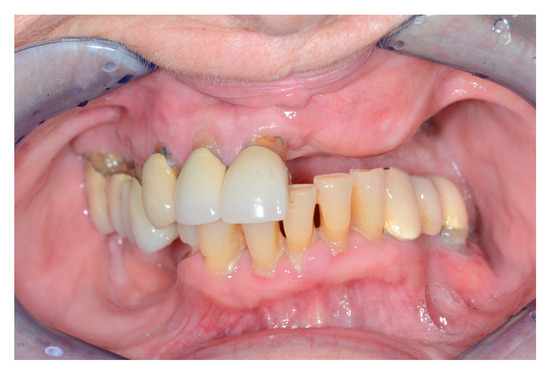

Figure 4. Intraoral view after alveolar ridge reconstruction.

Figure 5. Intraoral view with denture.